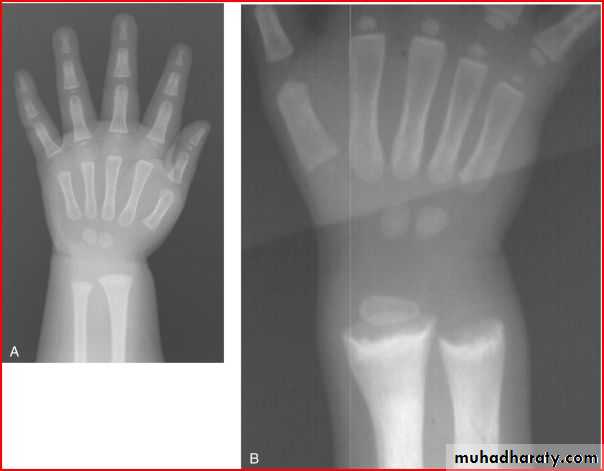

X ray of wrist showing cupping fraying splaying

Dx >>> rickettwo labrotary investigation 1. alkaline phosphatase elevation

2. s.calicium low or normal

ricket